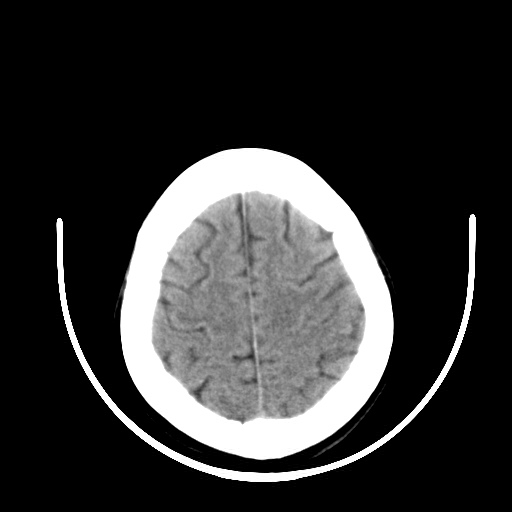

标题: CT16579:女 65岁间断性抽搐. [打印本页]

标题: CT16579:女 65岁间断性抽搐.

作者: zsl6918    时间: 2008-11-11 04:44

老年脑改变

右颞叶软化灶,右基底节区腔隙性脑梗塞;